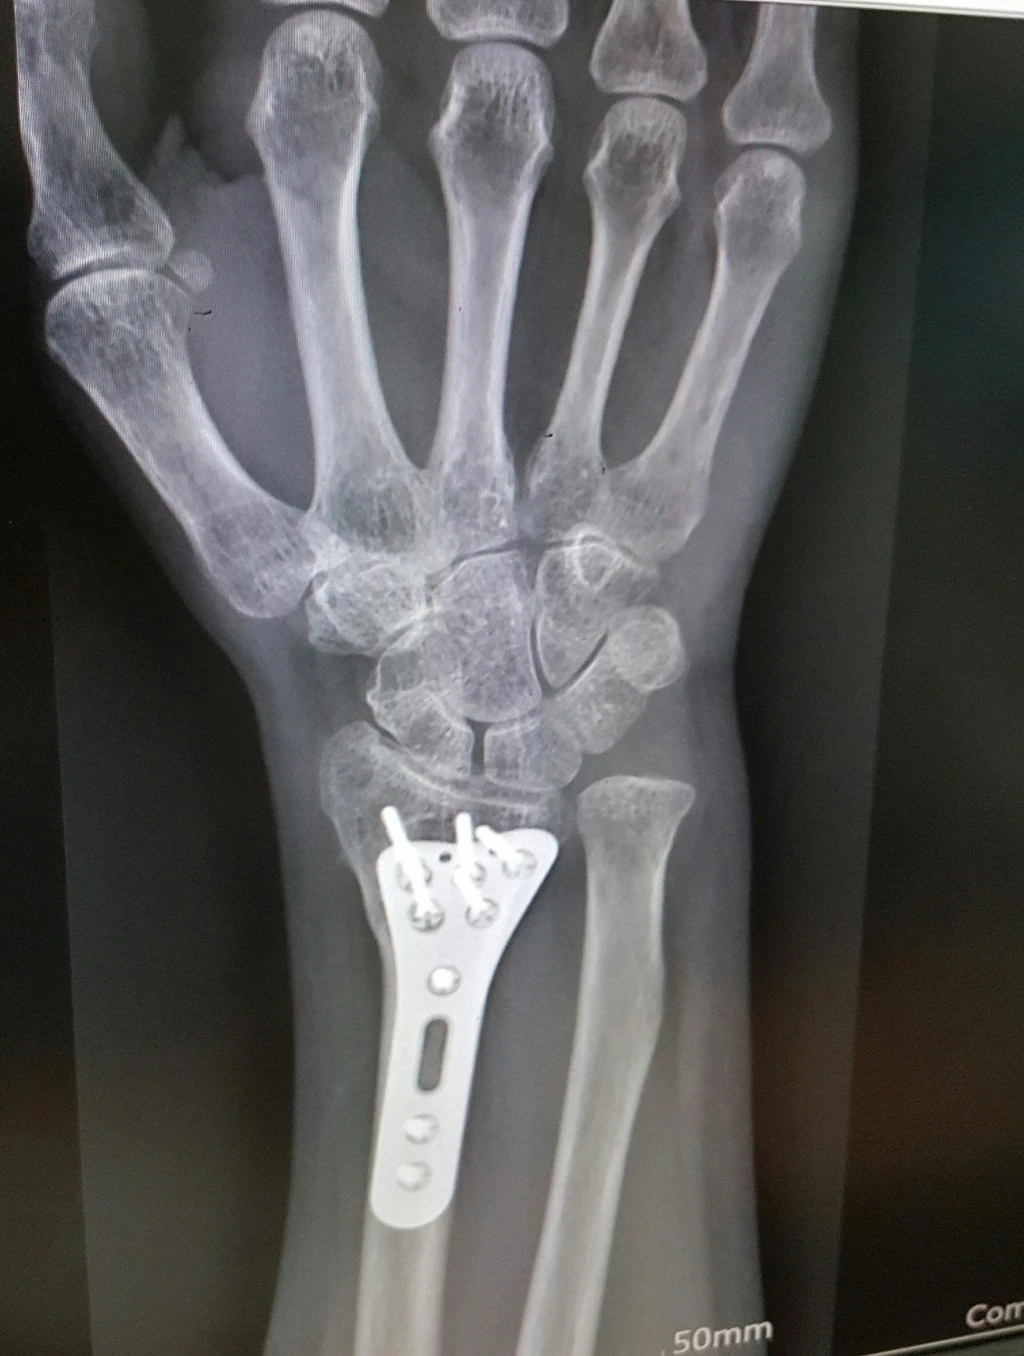

(철심 제거를 위해 입원)

뼈가 아주 야물딱지게 잘 붙었단다.

그래서 팔목의 철심 제거를 위해 입원을 했다.